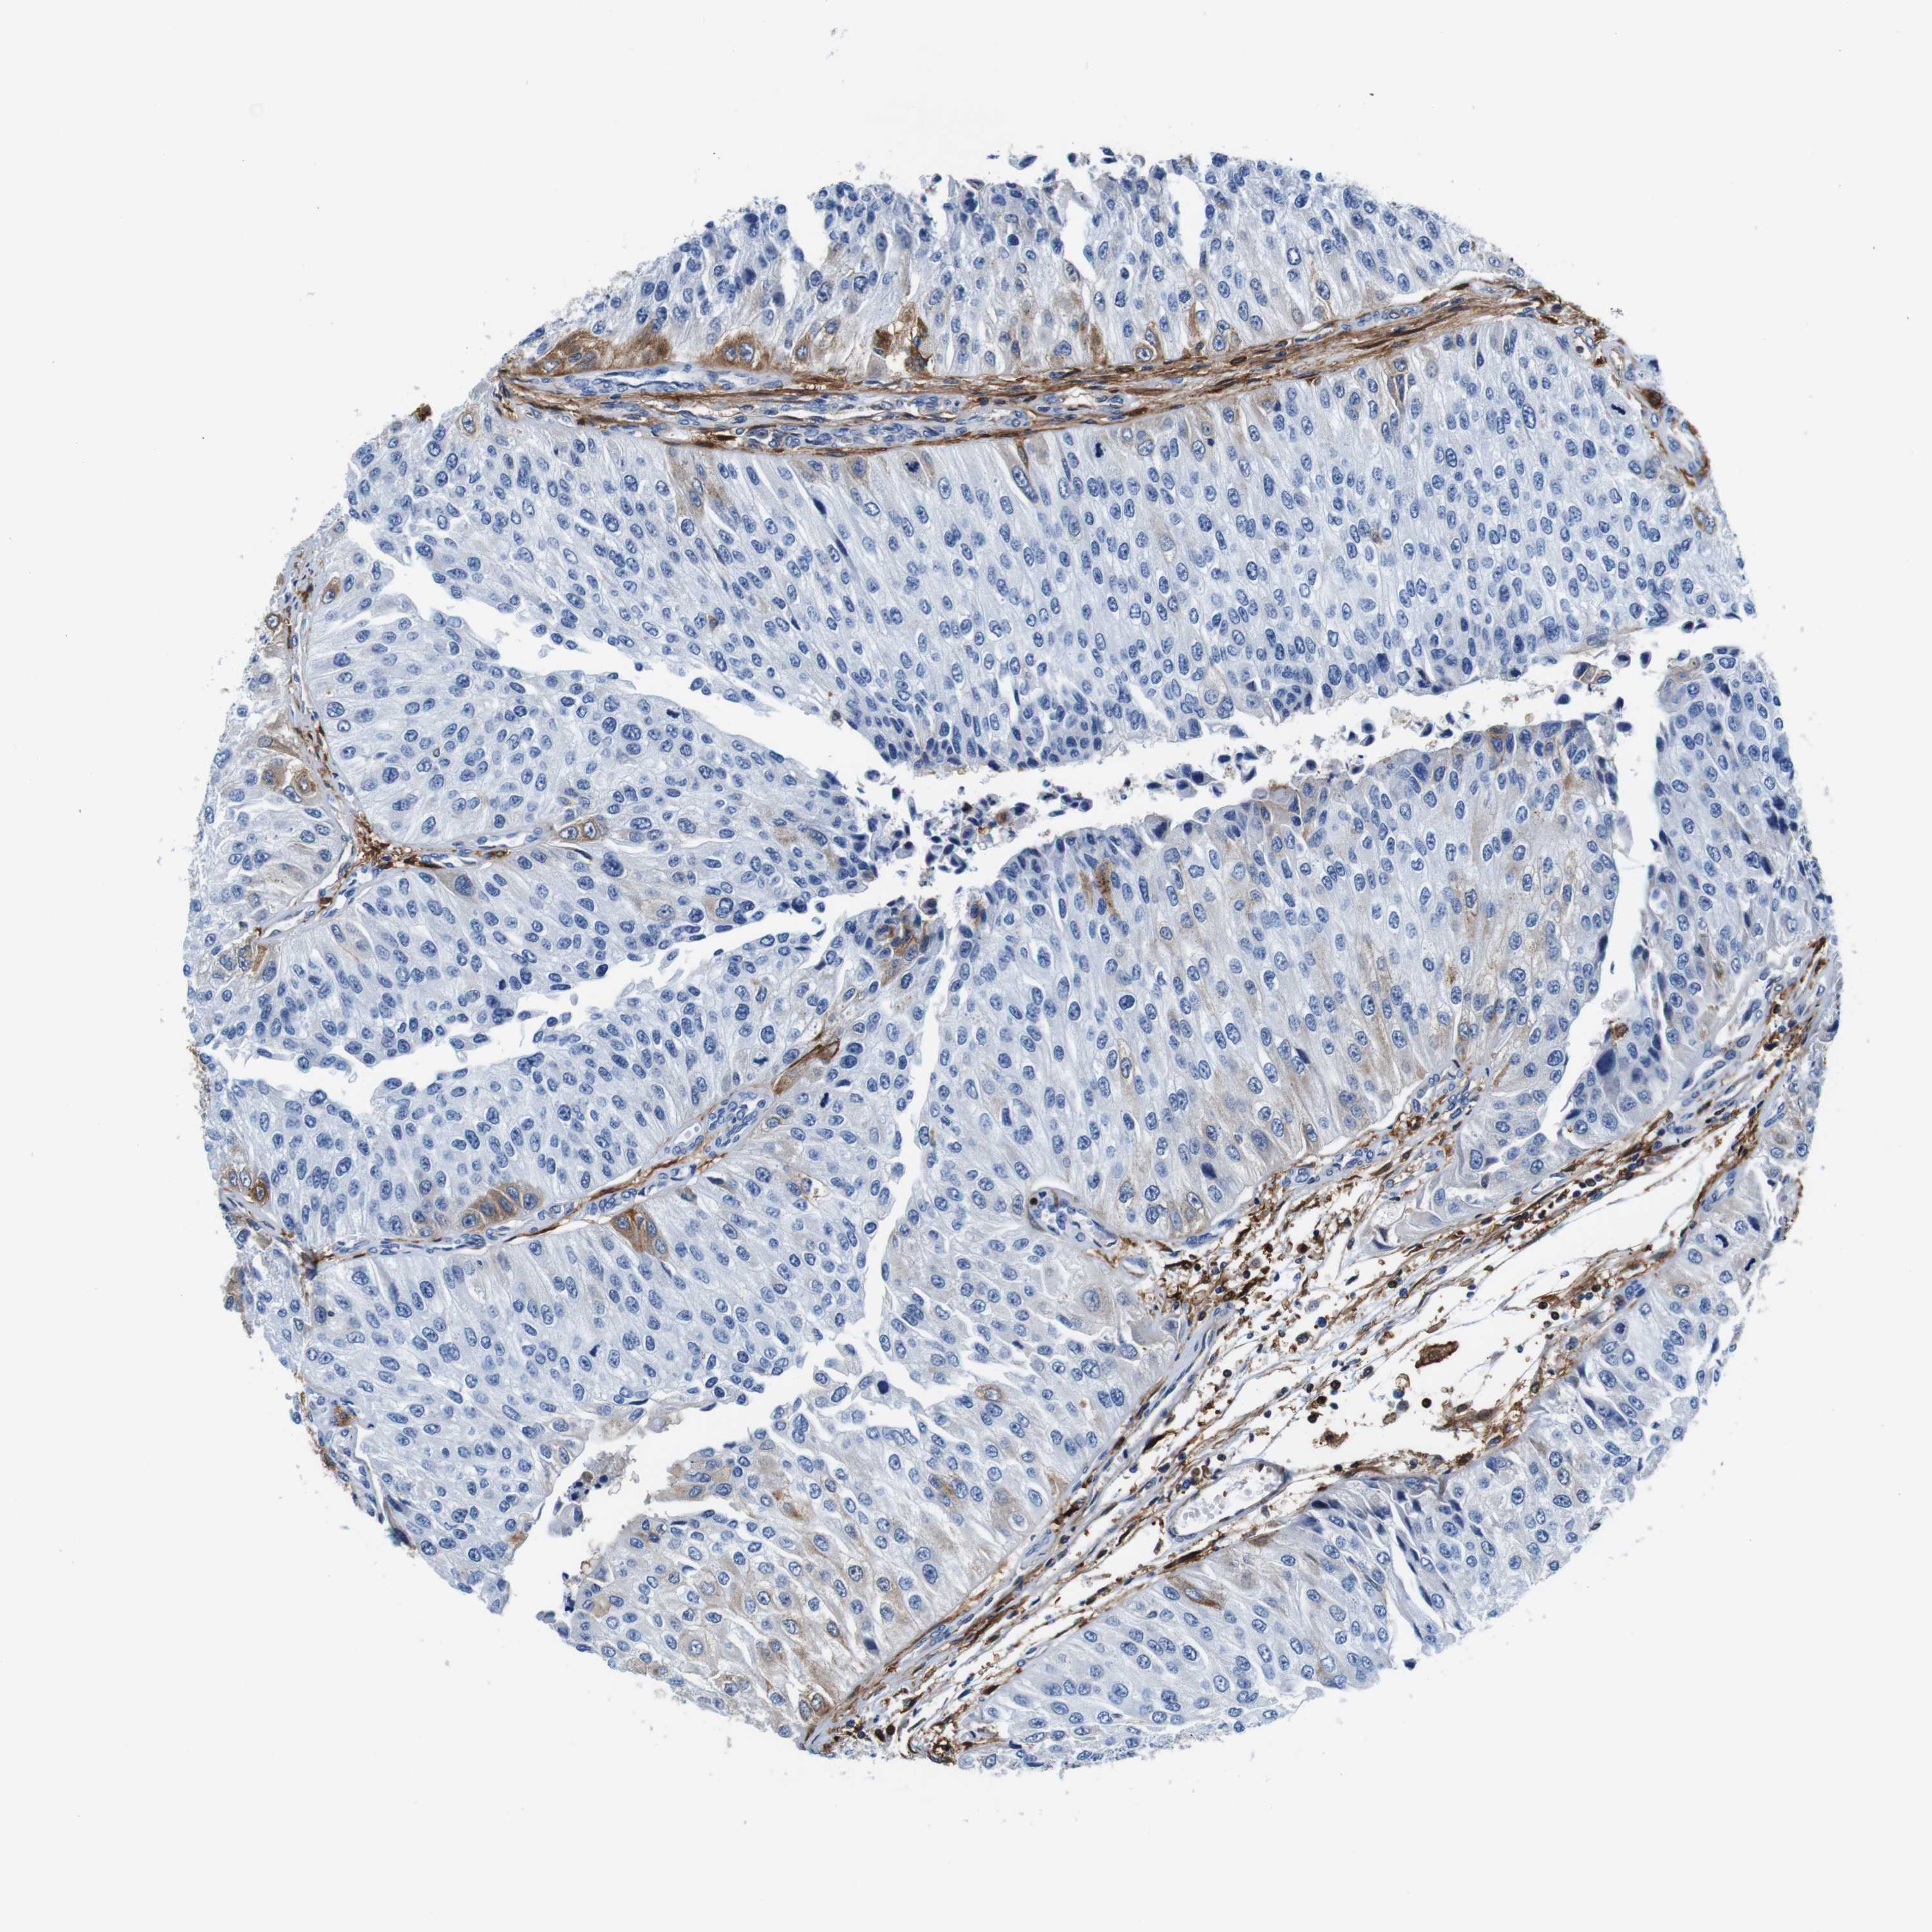

UROTHELIAL CANCER - Protein expressioni

A mouse-over function shows sample information and annotation data. Click on an image to view it in a full screen mode. Samples can be filtered based on level of antibody staining by selecting one or several of the following categories: high, medium, low and not detected. The assay and annotation is described here.

Note that samples used for immunohistochemistry by the Human Protein Atlas do not correspond to samples in the TCGA dataset.

Antibody stainingi

Antibody staining in the annotated cell types in the current human tissue is reported as not detected, low, medium, or high, based on conventional immunohistochemistry profiling in selected tissues. This score is based on the combination of the staining intensity and fraction of stained cells.

Each image is clickable and will lead to virtual microscopy that enables deeper exploration of all samples and also displays staining intensity scores, fraction scores and subcellular localization as well as patient and tissue information for each sample.

HPA011271

HPA011272

CAB013023

CAB035987

CAB058693

CAB080415

Staining

High

Medium

Low

Not detected

Intensity

Strong

Moderate

Weak

Negative

Quantity

>75%

75%-25%

<25%

None

Location

Nuclear

Cytoplasmic/membranous

Cytoplasmic/membranous,nuclear

Urothelial carcinoma, Low grade

Urothelial carcinoma, High grade

Urothelial carcinoma, NOS